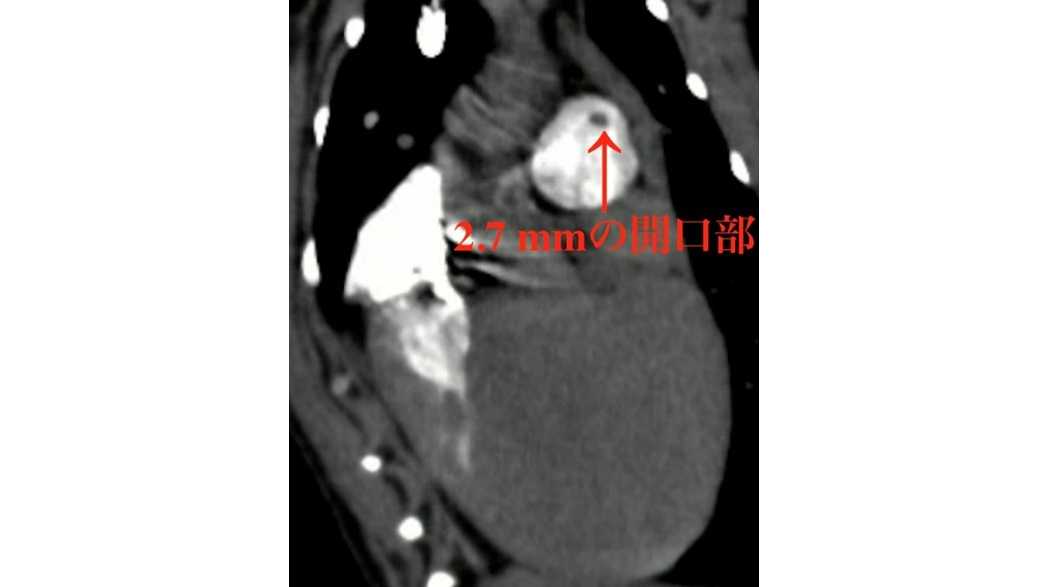

そこで我々は、この問題を解決するためにContinuous HIgh-Enhanced COntrast (CHIECO)法と名付けた特殊な心電同期CT造影検査法を開発し、直径2.7 mmの僅かな開口部を明瞭に描出することに成功しました。またそれだけでなく、非侵襲的に3次元的な血液の流れを可視化することも可能となりました。